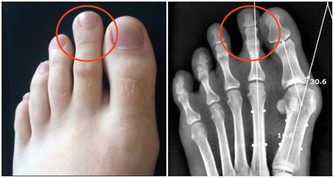

葫蘆素(英語:Cucurbitacin)是從中藥中提取,可治療肝炎及肝癌,存在於深綠色果類或果蒂部位,但誤食過量會有噁心、嘔吐、腹瀉等胃腸道症狀

人們在食用黃瓜時,因黃瓜把兒味苦而往往將其丟棄。其實,這種苦味是由其中含的一種叫葫蘆素的物質引起的,而葫蘆素C是難得的排毒養顏物質。更重要的是,葫蘆素可阻止肝細胞脂肪變性,抑制肝纖維增生,從而可預防原發性肝癌。

吃黃瓜時,一定不要把黃瓜把兒扔掉。黃瓜把兒的苦味來自其中含有的苦味素。這種苦味物質是一種葡萄甙,並認為有兩種異構體,黃瓜的苦味屬於 C型(叫做葫蘆素C)。這種叫葫蘆素C的物質,不僅存在於植物體內,而且存在於黃瓜果實的表皮內,葫蘆素C一般靠近果梗部分多,所以苦味較濃。

葫蘆素C能有效潤膚,減少皺紋,黃瓜本身豐富的維生素C,可起到抗衰老的作用,是難得的排毒養顏食品,且動物實驗證實,這種物質具有明顯的抗腫瘤作用。

黃瓜中含有的葫蘆素C具有提高人體免疫功能的作用,達到抗腫瘤目的。此外,該物質還可治療慢性肝炎和遷延性肝炎,對原發性肝癌患者有延長生存期作用。